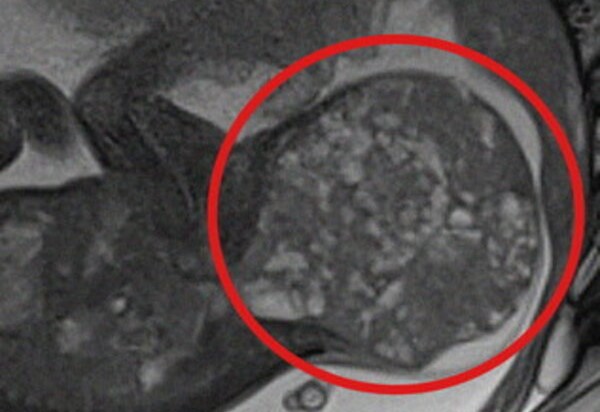

Alla nascita pesava quasi due chili, ma portava con sé un tumore di ben 800 grammi, pari a oltre la metà del suo peso corporeo effettivo (1,1 kg). Grazie a un intervento intrauterino salvavita, effettuato mentre era ancora nella pancia della mamma e, subito dopo il parto, a un’operazione chirurgica di rimozione della massa, oggi la piccola – nata prematura alla 30° settimana di gestazione – è in buone condizioni di salute e sta per tornare a casa con la famiglia.

La grande massa rimossa, un teratoma sacro-coccigeo, è una rara neoplasia che si sviluppa nella parte terminale della colonna vertebrale e colpisce circa 1 neonato ogni 35.000-40.000 nati vivi.

Pur essendo solitamente benigna, può comportare gravi complicanze per il feto. Tra queste il rischio di scompenso cardiaco, idrope fetale e morte intrauterina.

Nel caso specifico, alla 28° settimana di gestazione, a seguito di una rapida e improvvisa crescita della massa tumorale, gli specialisti dei due ospedali hanno deciso di intervenire in epoca fetale con una procedura mininvasiva di lasercoagulazione ecoguidata dei vasi sanguigni della massa stessa, eseguita presso il comparto operatorio del San Pietro Fatebenefratelli.

Dopo essere venuta alla luce, la neonata - che prima dell’intervento pesava 1,9 chili - è stata immediatamente operata per rimuovere completamente il teratoma di circa 800 grammi, pari ad oltre la metà del suo peso corporeo effettivo (1,1 kg).